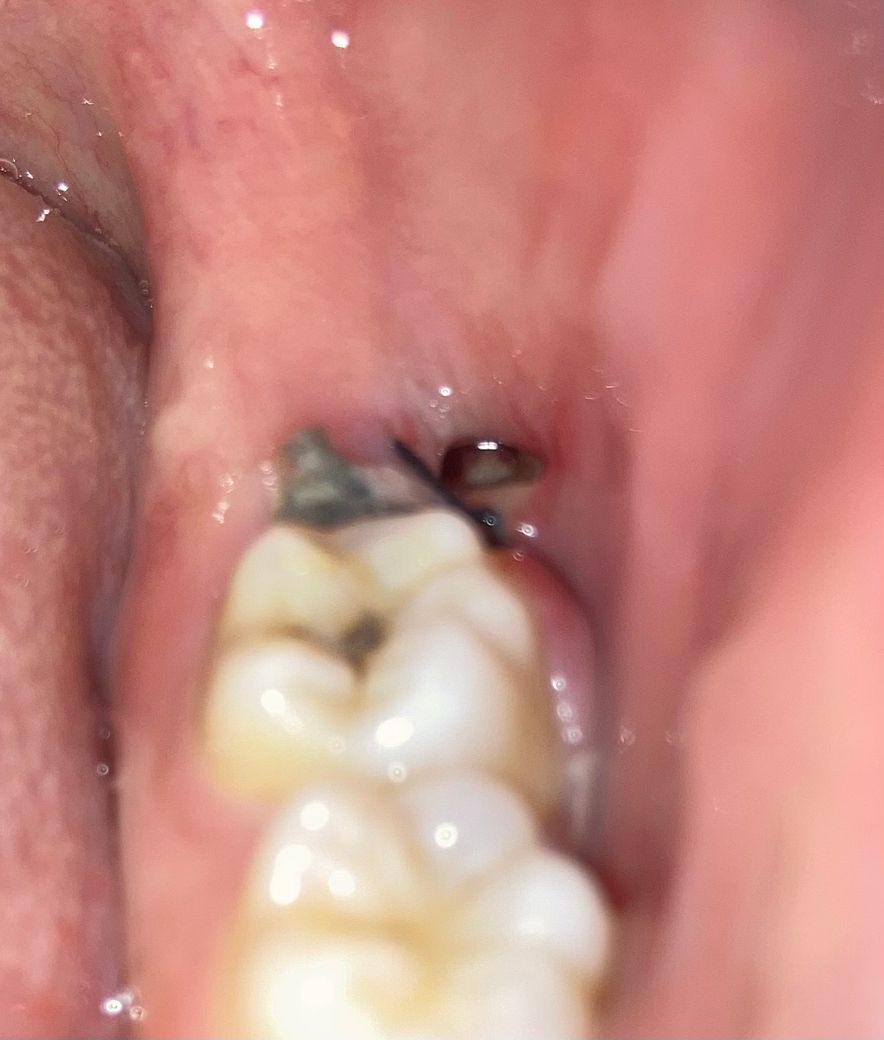

매복사랑니 20일에 발치했는데 혈병이 떨어진건가요?

발치 20일

첫번째 사진은 22일

두번째 사진 24일

인데 지금 혈병이 떨어지고 구멍이 생긴건가요?? 드라이 소켓 가능성이 높을까요 ㅠㅠ

혈병은 지혈만 잘되신거라면 크게 신경쓰지 않으셔도 됩니다. 드라이소켓도 아니고 잘 칭되고 있으니너무 걱정하지마세요.

발치한지 4일 경과후에 혈병이 떨어진 경우에는 문제가 되지 않습니다. 현재 발치부위에 구멍이 있는 것으로 나중에 잇몸이 차오르기에 걱정하지 않아도 됩니다.

정상치유과정에서 일어나는 잇몸 변화 양상으로 보여집니다

드라이소켓은 보통 극심한 통증과 악취를 동반하므로 이를 잘 확인해보시기 바랍니다